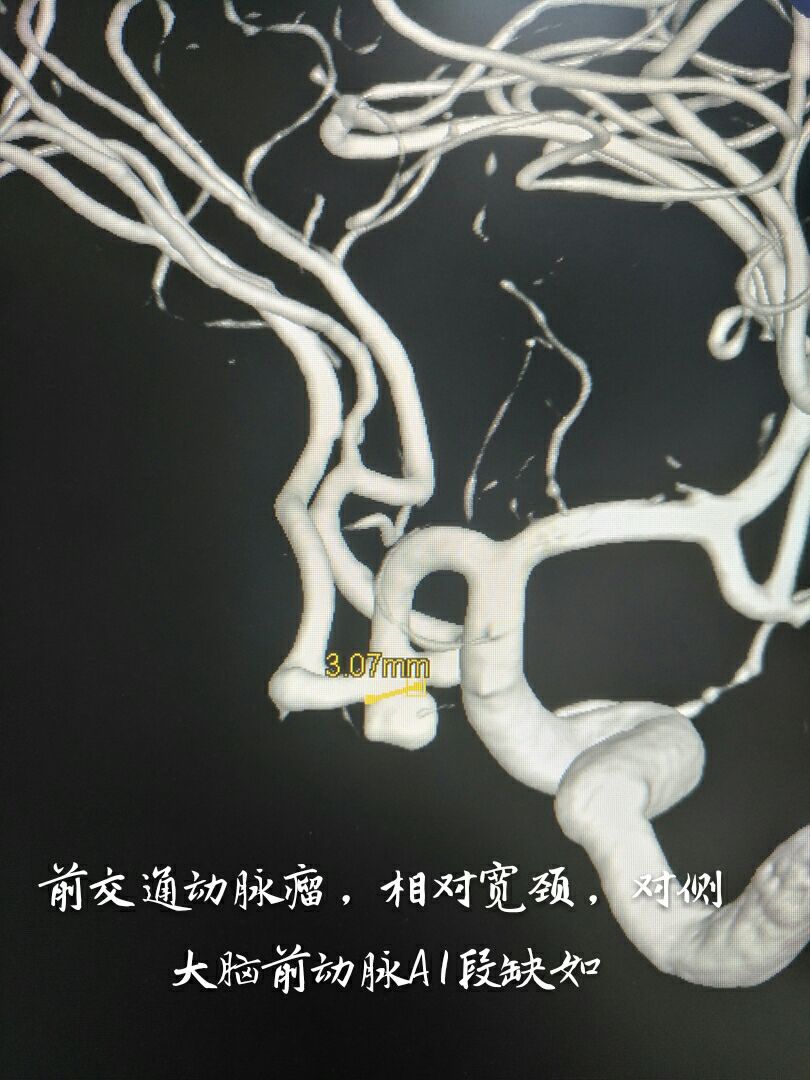

病例二:右侧前交通动脉瘤,宽颈,累及双侧大脑前动脉A2段

支架辅助下致密栓塞动脉瘤,难点:通络迂曲,使用8F GUIDING置于颈内动脉C2段,内套6F Navien置于海绵窦段完成